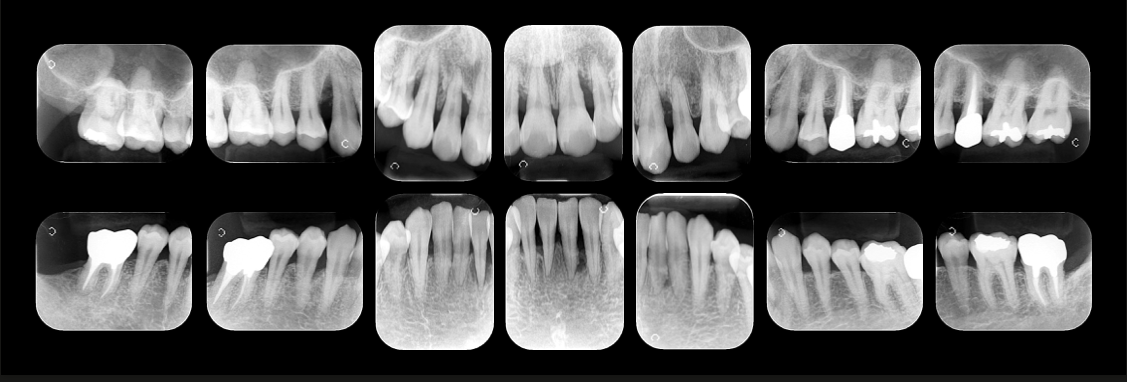

精密な診査診断

重度の歯周病で適切な治療計画を立案するためには、お口の状態を詳細に把握する必要があります。そのために当院では精密な診査診断を行います。歯周病の直接的な原因だけでなく、咬み合わせなどの間接的な原因も把握することによって、治療計画の精度が高まります。

治療例

重度歯周病の症例